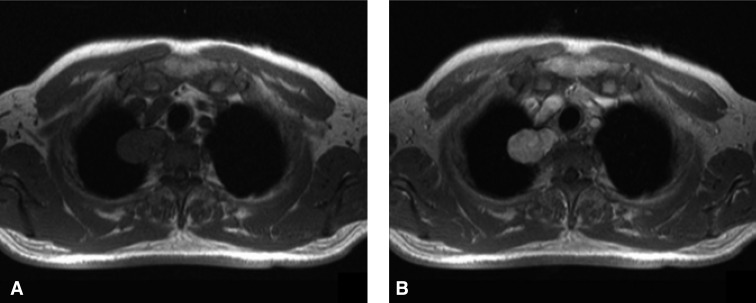

A 64-year-old man was referred to the pulmonary department of Korea University Ansan Hospital for an evaluation of a lung mass. He had received a medical checkup 1 month previously, when the mass-like lesion was incidentally found on plain chest X-ray. He was asymptomatic and had well controlled hypertension and diabetes; he also had a smoking history of 40 pack-years. On physical examination, no palpable lymphadenopathy or other abnormality was noted. His hemoglobin, white cell count, platelets, urea and electrolytes, glucose, liver function tests, and serum calcium were normal. The plain chest X-ray revealed a smooth marginated 3×4 cm sized mass-like lesion in the right upper mediastinal area (Figure 1A). Chest computerized tomographic (CT) studies, performed after the intravenous administration of a contrast agent, revealed a 2.5×2 cm sized, well defined, bilobed, homogeneously enhancing mass lesion in the right upper posterior mediastinum (Figure 1B). No definite evidence of bony erosion of the thoracic vertebrae was observed. On magnetic resonance imaging (MRI), the tumor was visualized as a homogeneous signal intensity mass with a signal intensity similar to muscle on T1-weighted images, whereas on T2-weighted images, the signal intensity was moderately higher than that of muscle. Moderate heterogeneous enhancement was noted with gadolinium-enhancement (Figure 2).

Figure 2

Magnetic resonance imaging (MRI) revealed a tumor of homogeneous signal intensity with a signal intensity similar to that of muscle on T1-weighted images (A). Moderate heterogeneous enhancement was observed after introducing gadolinium contrast (B).